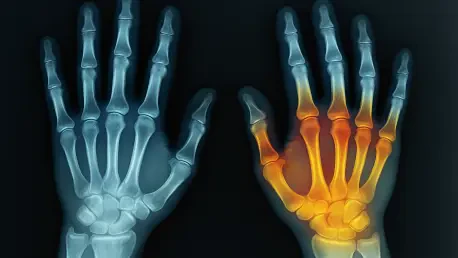

Diagnosing vascular conditions in the delicate and complex anatomy of a child’s hand has long presented a formidable challenge, balancing the urgent need for clear images with the critical imperative to protect young patients from excessive radiation. Recent breakthroughs in pediatric radiology, however, are fundamentally reshaping this landscape by leveraging dual-energy computed tomography (DECT) combined with virtual monoenergetic images (VMIs). This advanced approach, explored in foundational research, promises not only to elevate diagnostic precision but also to uphold the most stringent safety protocols vital for pediatric care. The technology’s ability to overcome the inherent difficulties of imaging intricate vascular networks in children marks a pivotal advancement, offering a far safer and more effective alternative to traditional methods and setting a new precedent for clinical outcomes.

Dual-energy computed tomography emerges as a powerful and elegant solution to the long-standing challenges of pediatric angiography. The technology operates by employing two distinct X-ray energy levels simultaneously during a single scan, a capability that allows it to differentiate various materials within the body based on their unique energy attenuation characteristics. This is particularly advantageous in angiography, as it enables the system to create a superior visualization of contrast-enhanced vascular structures, clearly distinguishing them from surrounding bone and soft tissue with a level of clarity not achievable with conventional single-energy CT. This foundational ability to separate materials provides a much cleaner dataset from the outset, paving the way for more sophisticated image processing and analysis without subjecting the child to additional procedures or higher initial radiation doses.

The true innovation of this approach is fully realized when the data acquired from the dual-energy scan is computationally processed to generate virtual monoenergetic images. VMIs are sophisticated reconstructions that simulate the images that would have been produced by a theoretical, perfect single-energy X-ray beam. This process gives radiologists the unprecedented ability to retrospectively select the optimal kiloelectron volt (keV) level that best highlights the specific tissue of interest. For hand angiography, this means they can fine-tune the image to maximize the contrast of the iodine-filled blood vessels, making them stand out vividly against the background anatomy. As a result, the conspicuity of vessels and potential pathologies is significantly enhanced, achieving diagnostic excellence without any increase in the administered radiation dose or the volume of contrast media.

The multifaceted benefits of applying DECT with VMIs in pediatric hand angiography were underscored by the core findings of recent research. A primary advantage identified was the substantial improvement in overall image clarity and anatomical detail. VMIs provide an enhanced level of contrast resolution that is vital for accurately delineating the fine vascular architecture of the pediatric hand, a task that has often been fraught with difficulty using older technologies. This heightened precision allows for the confident identification of very subtle vascular malformations that might otherwise be obscured in conventional scans. Simultaneously, the technology proved remarkably effective in reducing image-degrading artifacts, including those caused by slight patient motion, which ultimately resulted in higher-quality diagnostic images and a significantly lower likelihood of requiring repeat procedures.